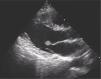

A 41-year-old man presented to the cardiovascular department with paroxysmal twinges in the left chest for three days. The initial chest radiograph, 12-lead electrocardiogram and laboratory findings were unremarkable. Transthoracic echocardiography revealed a 10.6 mm × 8.3 mm mobile mass attached to the anterior mitral leaflet (Figure 1). Because of the potential systemic embolic risk, the patient was referred for complete surgical removal. On operative inspection, the lesion was between the anterior mitral leaflet and primary chordae (Figure 2). A mitral valve repair (28 mm ring annuloplasty, triangular resection of the anterior leaflet and new chordae formation) with complete excision of the mass was undertaken. The mass had a sea-anemone appearance with frond-like projections after immersion in saline solution (Figure 3). The histopathologic examination confirmed a papillary fibroelastoma. The patient's postoperative course was uneventful. Six months after the operation, the patient's clinical findings were normal, without evidence of recurrence by transthoracic echocardiography.